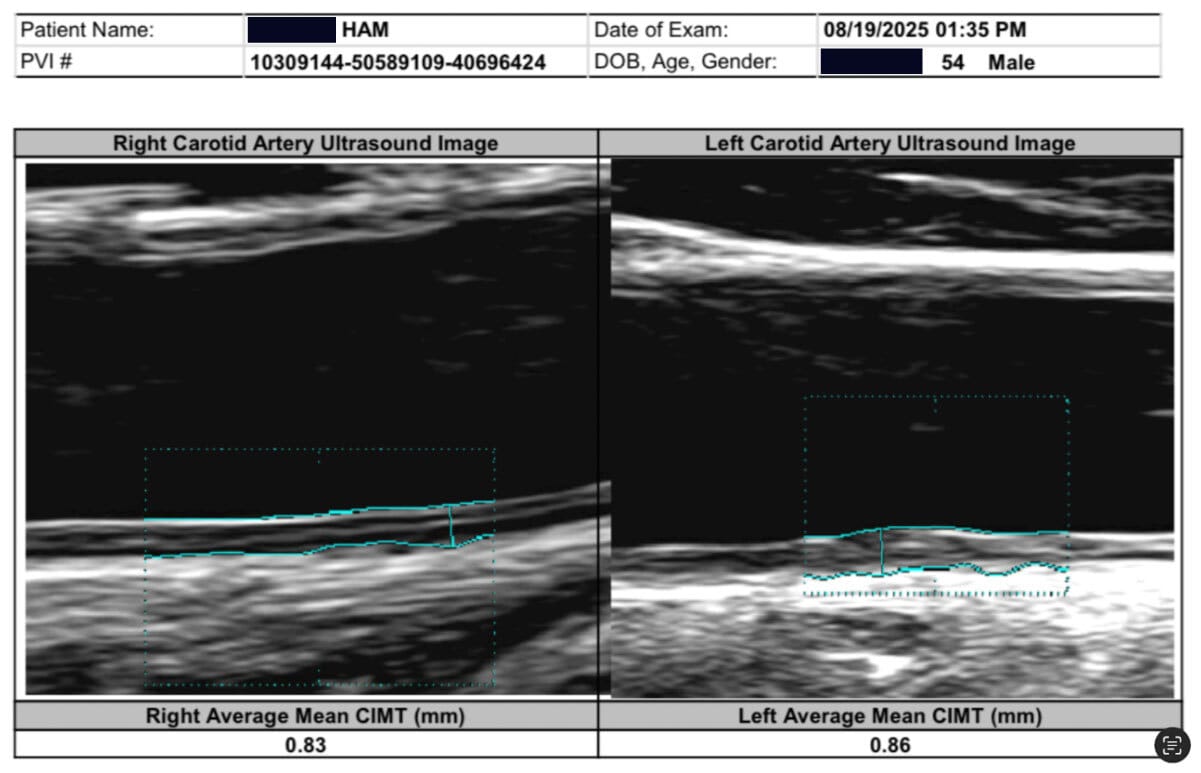

Here is my carotid ultrasound on August 19, 2025. No more plaque! And CIMT is 0.86mm.

25% plaque → 0% plaque

CIMT 1.4mm → 0.86 mm (38% reduction) in 3 months

Note that for my age of 55, a CIMT > 0.837mm is abnormal. I went from 1.4mm (worse than an 85 year old) to high normal for my age. I was so happy to be average.

And still no plaque visualized in both carotid vessels!